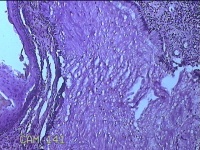

宫颈赘生物

性别

女

年龄

37岁

临床诊断

早期人工流产;宫颈炎性疾病

一般病史

宫颈有1赘生物。

标本名称

大体所见

灰白暗红色肿物1.3x0.8x0.2cm一个,表面糜烂。